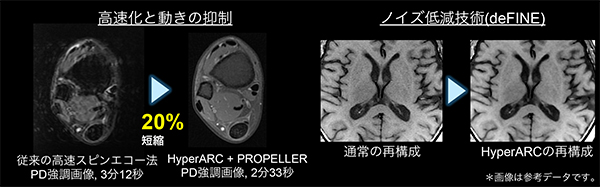

HyperARC(ハイパーアーク)

動きに強いパラレルイメージング法ARCとノイズ低減技術deFINEを組み合わせることで画質の低下を抑えながら高速化が実現できる新しい2D/3D高速撮像技術です。動き補正PROPELLER MBや圧縮センシング(HyperSense)との併用も可能です。

圧縮センシング技術を応用して少ないデータサンプリングから高分解能画像を再構成することで,スキャン時間を大幅に短縮するアプリケーションです。

従来のパラレルイメージング法は,高い倍速を用いるとアーチファクトやSNRの低下が見られますが,HyperSenseはこれらの影響を受けず,全身領域において短時間で高分解能ボリュームイメージングを提供します。